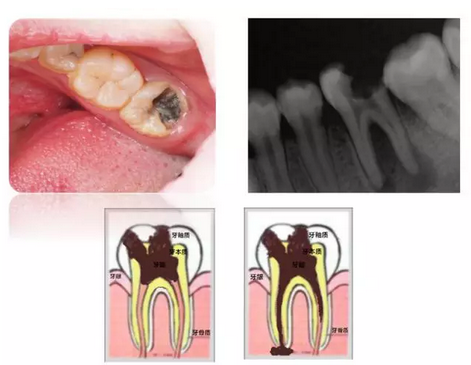

1、齲齒,也就是蛀牙,蟲牙,表現為(wei) 在牙齒上有黑色的斑點,而且刷牙去不掉,使勁刷也沒用。一般隻有通過治療後才能去除的。

別看這種牙齒看起來是黑色的,其實下麵可能是很深的牙洞,需要帶孩子到醫院拍片檢查,確定是否傷(shang) 到牙齒裏麵的牙神經,如果沒有傷(shang) 到,可以進行充填補牙治療,也就是去除這些黑色的感染的牙齒組織,然後使用樹脂等材料把這個(ge) 洞填補起來。得到修複牙齒缺損和外在形態的結果。